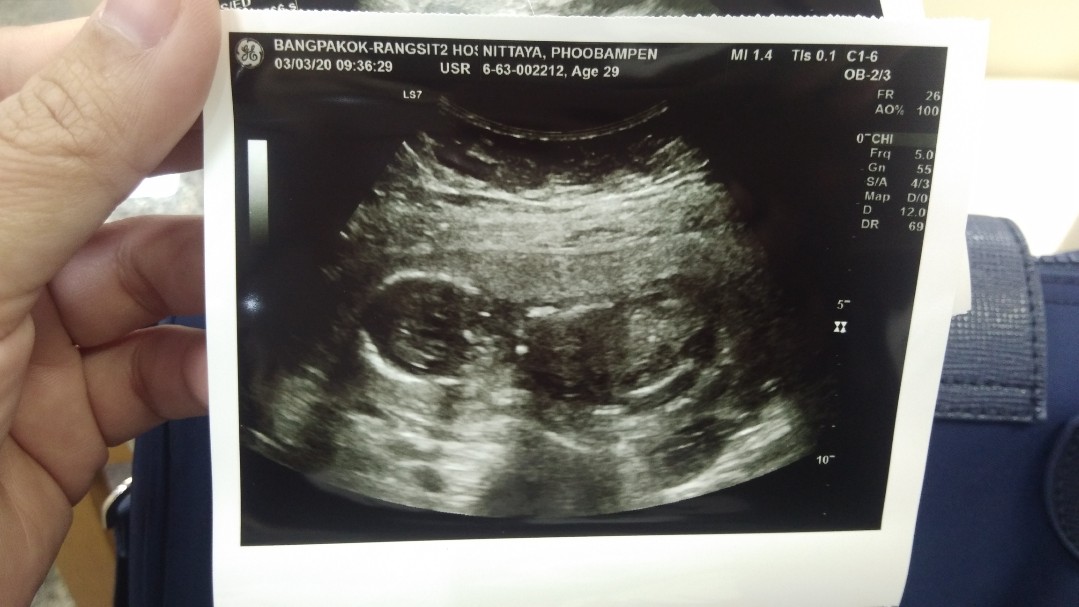

14 วีคค่ะ